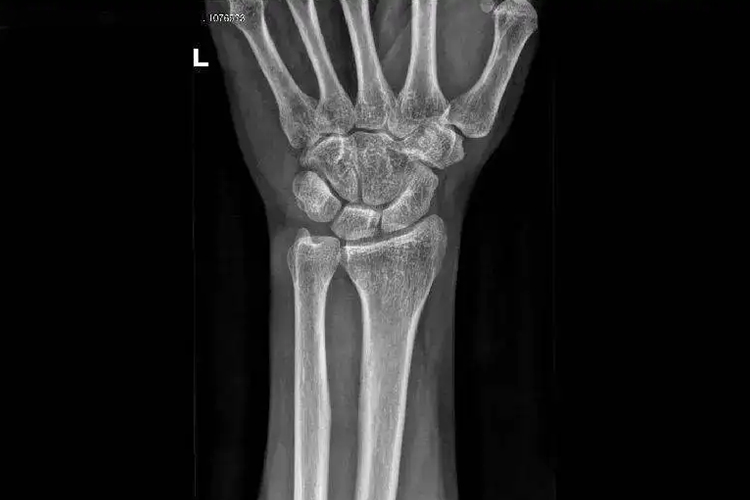

正常的手腕骨骼X光,属于一种影像学检查,是腕部病变常用的检查手段,检查可见正常的桡腕关节、腕骨间关节及腕掌关节。

正常的手腕关节包括桡腕关节、腕骨间关节及腕掌关节。腕骨有8块,分近、远两排,自桡侧向尺侧近排腕骨为舟状骨、月骨、三角骨和豌豆骨,远排腕骨为大多角骨、小多角骨、头状骨和钩状骨,8块腕骨之间形成腕骨间关节。

正常桡骨远端关节面向掌侧倾斜前倾角9°-20°,平均14°,向尺侧倾斜20°-35°,平均27°。桡骨远端关节面、舟状骨、月骨近端关节面和三角纤维软骨复合体构成桡腕关节。